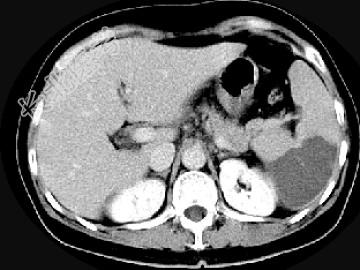

- 单项选择题女,54岁, 左上腹痛,CT检查如图, 最可能的诊断是 ( )

A、脾淋巴瘤

B、脾脓肿

C、脾梗死

D、脾血管瘤

E、脾转移癌